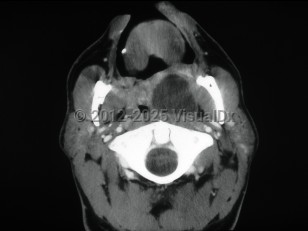

Sore throat, Cervical lymphadenopathy, 50-59 year old Female

EpiglottitisEpiglottitis

Retropharyngeal abscess